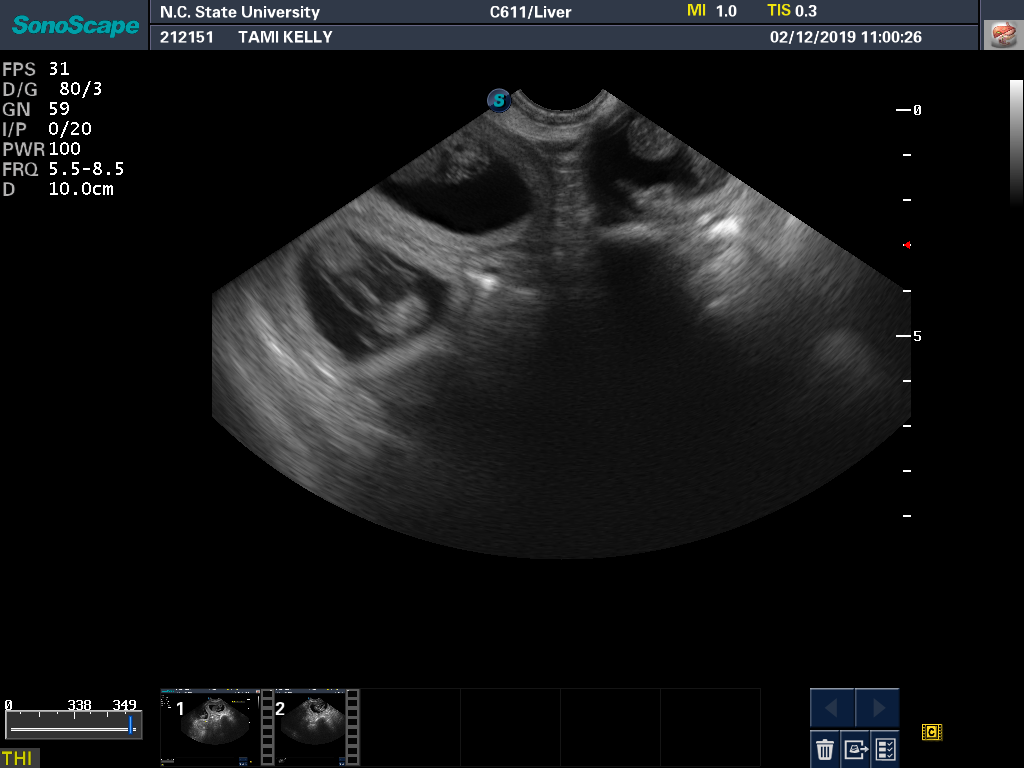

Tami had another ultrasound and progesterone check. All looks well. Here is a a good view of one of the puppies from the ultrasound monitor. And a view showing that there really are three puppies.